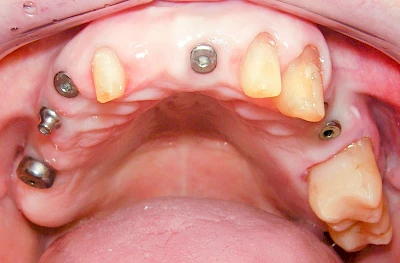

Implantate: Kronen & Brücken

Fehlen einzelne Zähne und die Nachbarzähne sind unbeschadet oder gut zahnärztlich versorgt, werden immer häufiger Implantate gewählt, um die Lücken zu schließen. Auch bei größeren oder verteilten Lücken, wenn keine herausnehmbare Prothese gewünscht ist, werden Implantate für Kronen- bzw. Brückenversorgungen gesetzt. In Einzelfällen entscheiden sich sogar zahnlose Patienten für eine festsitzende Versorgung auf Implantaten.

Varianten zur Verankerung von festsitzendem Zahnersatz auf Implantaten